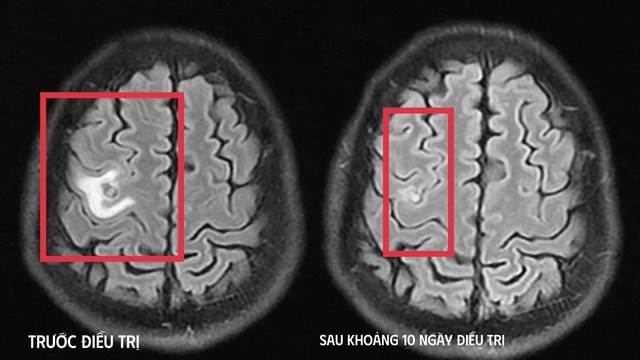

Kết quả chụp cộng hưởng từ (MRI) sọ não cho thấy một tổn thương dạng nang nhỏ tại thùy trán trái, kích thước khoảng 11 x 7 mm, xung quanh có phù não nhẹ. Hình ảnh này gợi ý nhiều đến tổn thương do ký sinh trùng hơn là u não nguyên phát.

Sau khoảng 10 ngày điều trị nội trú, tình trạng bệnh cải thiện rõ rệt như hết tê tay, không còn cơn co giật, không đau đầu hay chóng mặt, toàn trạng ổn định. Người bệnh được cho ra viện và tiếp tục điều trị ngoại trú đủ liệu trình kéo dài 4 tuần.

Khi tái khám gần một tháng sau, phim MRI cho thấy tổn thương não thu nhỏ rõ rệt, phù não giảm, không còn dấu hiệu tiến triển, chứng tỏ đáp ứng điều trị tốt. Bệnh nhân được chỉ định thêm một đợt thuốc củng cố và theo dõi lâu dài.